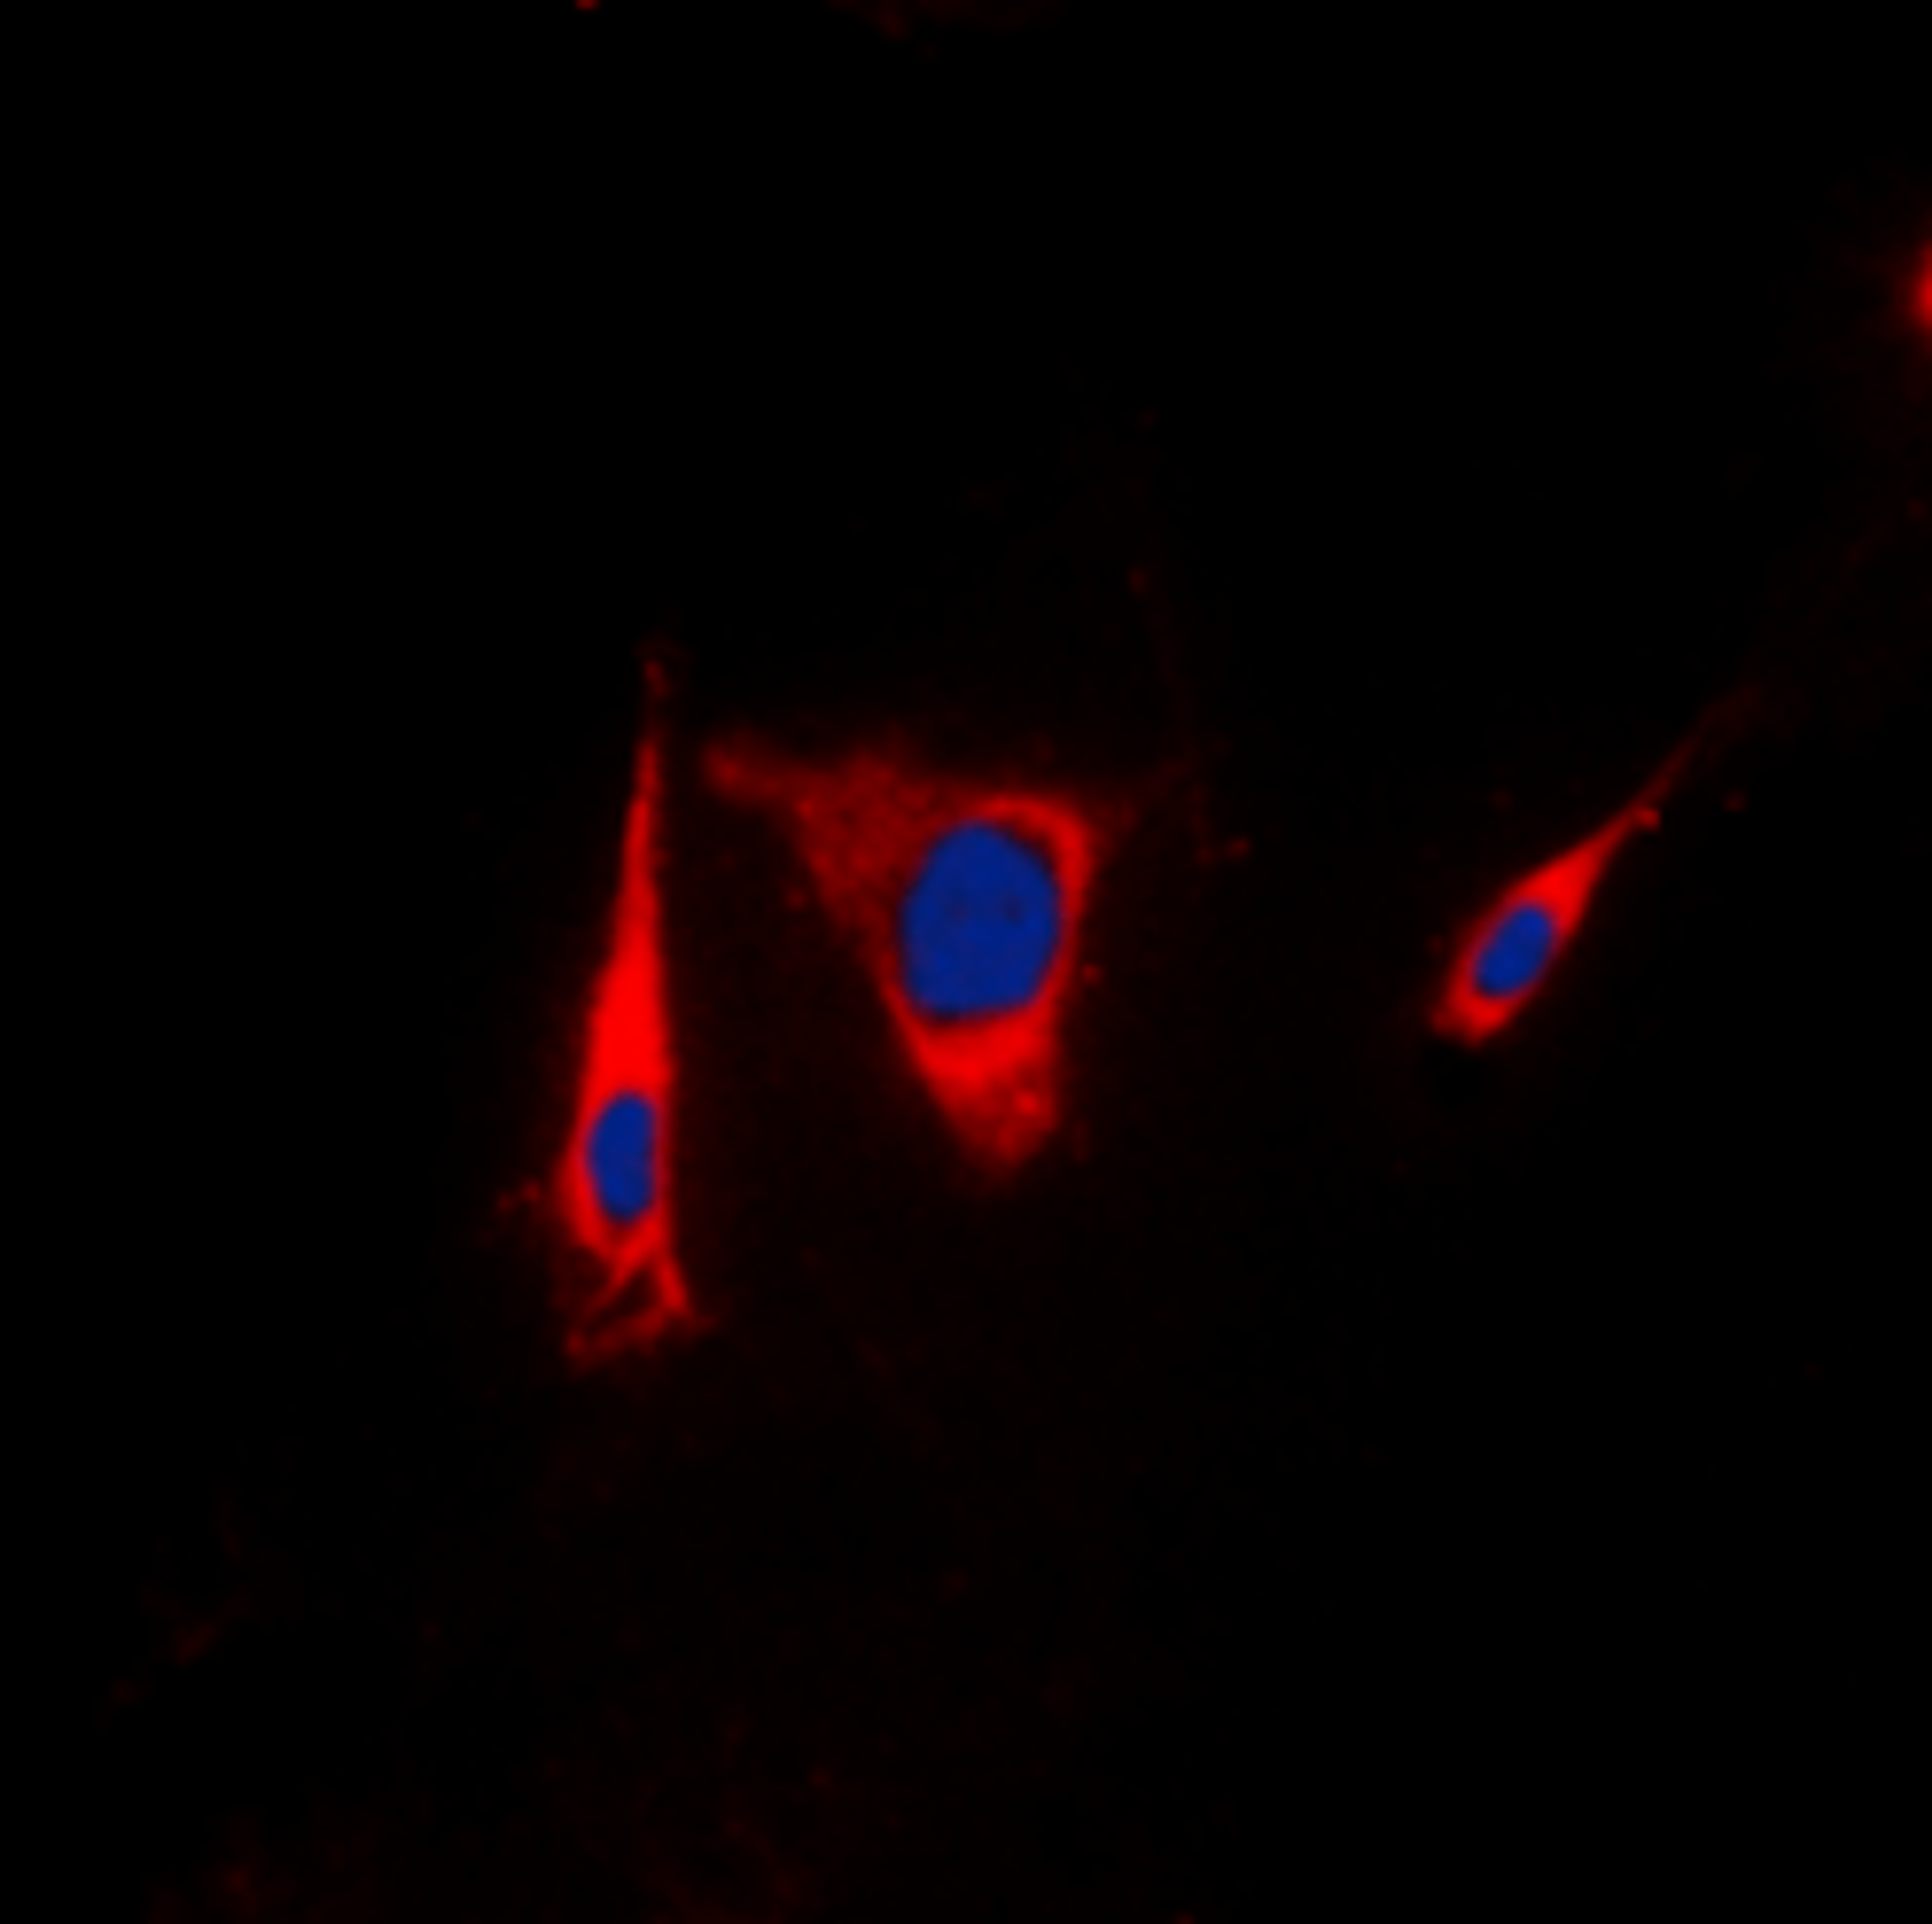

Estrogen Receptor beta antibody

- orb389114

- Host

- Mouse

- Reactivity

- Horse (Equine), Human, Monkey, Pig (Swine), Rat

- Applications

- Flow Cytometry, Immunofluorescence (Paraffin-Embedded Sections), Immunohistochemistry (Paraffin-Embedded Sections), Western Blotting